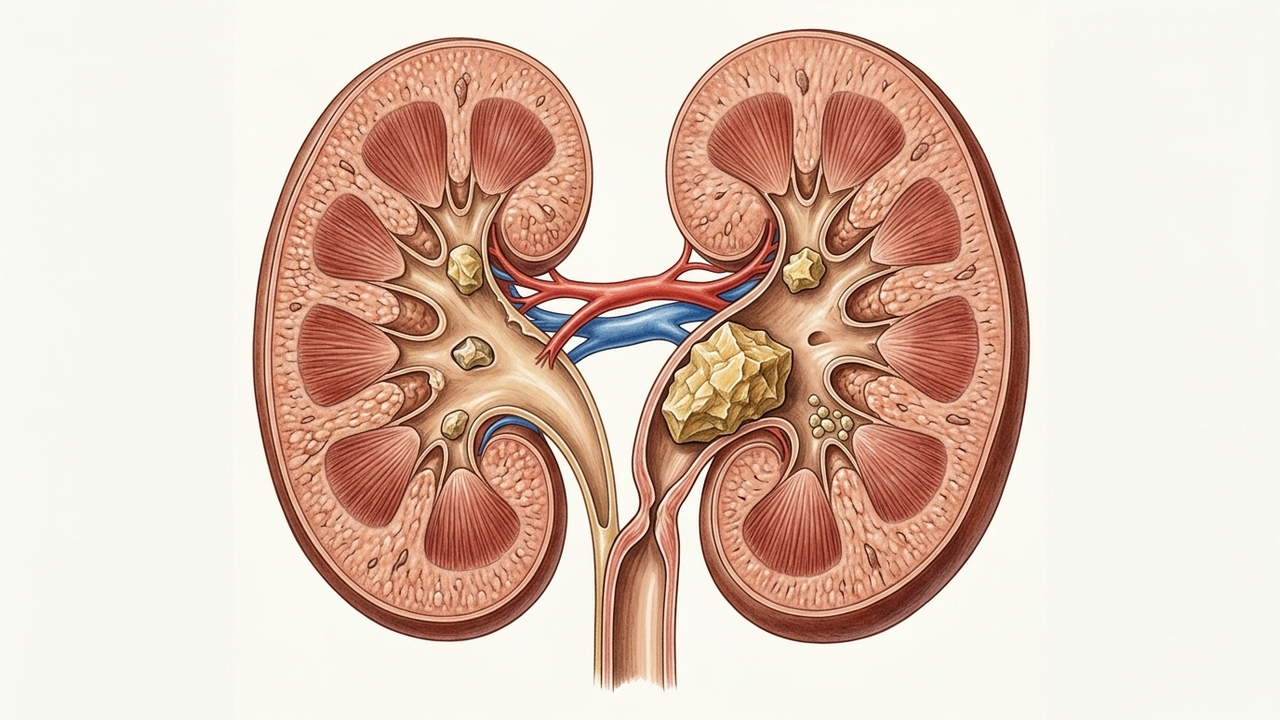

O tomate costuma aparecer em listas de alimentos “proibidos” para quem tem medo de problemas renais, mas essa ideia não se sustenta na prática. A relação entre tomate e pedra nos rins é cercada de confusão e exagero. O que muita gente não sabe é que, na maioria dos casos, o tomate pode até ajudar na prevenção em vez de causar o problema.

Esse mito está ligado à presença de oxalato, um composto que pode contribuir para a formação de cálculos em situações específicas. Como as sementes do tomate contêm pequenas quantidades dessa substância, surgiu a associação.

No entanto, o consumo comum não representa risco significativo. Para que houvesse impacto real, seria necessário ingerir quantidades muito acima do normal, o que não faz parte da rotina da maioria das pessoas.

Na prática, o tomate pode ter um efeito positivo. Ele é rico em potássio, um mineral que contribui para o equilíbrio do organismo e ajuda na eliminação de substâncias que poderiam formar cálculos.

Além disso, o potássio favorece a presença de citrato na urina, um elemento que atua como protetor natural contra a formação de pedras nos rins.